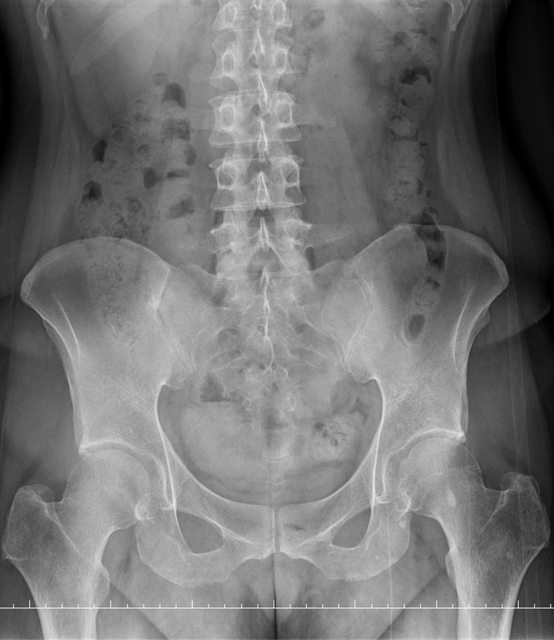

https://i.imgur.com/9HfkOHc.png

骨盆 https://i.imgur.com/h7KknkX.png

股骨頭放大特寫...左邊是右股骨 你覺得哪邊比較正常? https://i.imgur.com/16erxqZ.png

https://i.imgur.com/7NtJDKg.png

醫生似乎很急 就問了二個問題就叫我去照X光 可能就一分鐘吧 回來看了下X光就說可能有神經壓迫 又是14天的消炎止痛藥 說還會痛再來回診或去看脊柱專科或復健科 感覺就是浪費了一天的時間排隊再排隊 沒得到答案 也沒有得到解決... 然後拿了吃越多可能洗腎越快的止痛藥 會不會下次脊柱專科也開14天消炎止痛說如果還有問題叫你去掛神經科? 為何不給我照MRI呢?我第一次去看問了MRI就還是只給我照X光 1.2期X光照了也不一定有異常,我實在不懂不用MRI的邏輯 體驗實在太差了,當然我也知道當有一百號排隊時問診就不可能細到哪怕只有15分 我想不等直接掛看看禮拜三神經科會怎解釋了 ※ 編輯: capybaradash (118.166.44.25 臺灣), 07/31/2023 14:29:17 ※ 編輯: capybaradash (118.166.44.25 臺灣), 07/31/2023 14:37:27

看了下治療方法,那有看等於沒看了 照MRI似乎也是白做,自費照根本浪費 其實X光以我外行人放大好幾倍看過去,左股骨跟大腿骨明顯狀態較差 不清楚醫生是不是有鷹眼,小小一張看過去就說沒什問題 我是不會去考慮手術的 小時候骨折都是看國術館 還減壓股頭打孔...開刀100%NO 治療方法 1.拐杖 2.藥物治療(1)非類固醇類消炎止痛藥(NSAID) (2)口服雙磷酸鹽類藥物 (3)血管擴張劑 (4)高壓氧 目前股骨頭缺血性壞死的治療,根據現有的證據,仍然以手術為主流。 於早期(第一、二期),尚未塌陷的股骨頭缺血性壞死,髖關節減壓手術值得一試, 至於第三、甚至第四期股骨頭缺血性壞死,人工髖關節置換術能夠有效的解除疼痛以及恢 復行走負重的功能。 ※ 編輯: capybaradash (118.166.44.25 臺灣), 07/31/2023 16:04:20

g17321732: 1.骨頭看起來沒大問題,x光不是放大找不一樣這麼簡單 07/31 18:18

g17321732: 3.MRI對你的幫助不大,X光已經足夠清楚,不用花冤枉錢 07/31 18:18

yasmine1030: 人體不是百分百對稱我實在看不出你X光兩邊股骨有何差 08/01 01:29